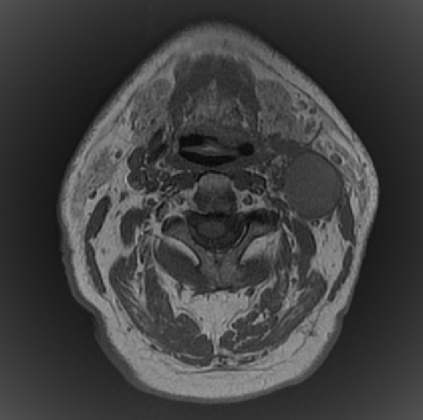

Organ at risk (OAR) segmentation is a critical process in radiotherapy treatment planning such as head and neck tumors. Nevertheless, in clinical practice, radiation oncologists predominantly perform OAR segmentations manually on CT scans. This manual process is highly time-consuming and expensive, limiting the number of patients who can receive timely radiotherapy. Additionally, CT scans offer lower soft-tissue contrast compared to MRI. Despite MRI providing superior soft-tissue visualization, its time-consuming nature makes it infeasible for real-time treatment planning. To address these challenges, we propose a method called SegReg, which utilizes Elastic Symmetric Normalization for registering MRI to perform OAR segmentation. SegReg outperforms the CT-only baseline by 16.78% in mDSC and 18.77% in mIoU, showing that it effectively combines the geometric accuracy of CT with the superior soft-tissue contrast of MRI, making accurate automated OAR segmentation for clinical practice become possible. See project website https://steve-zeyu-zhang.github.io/SegReg